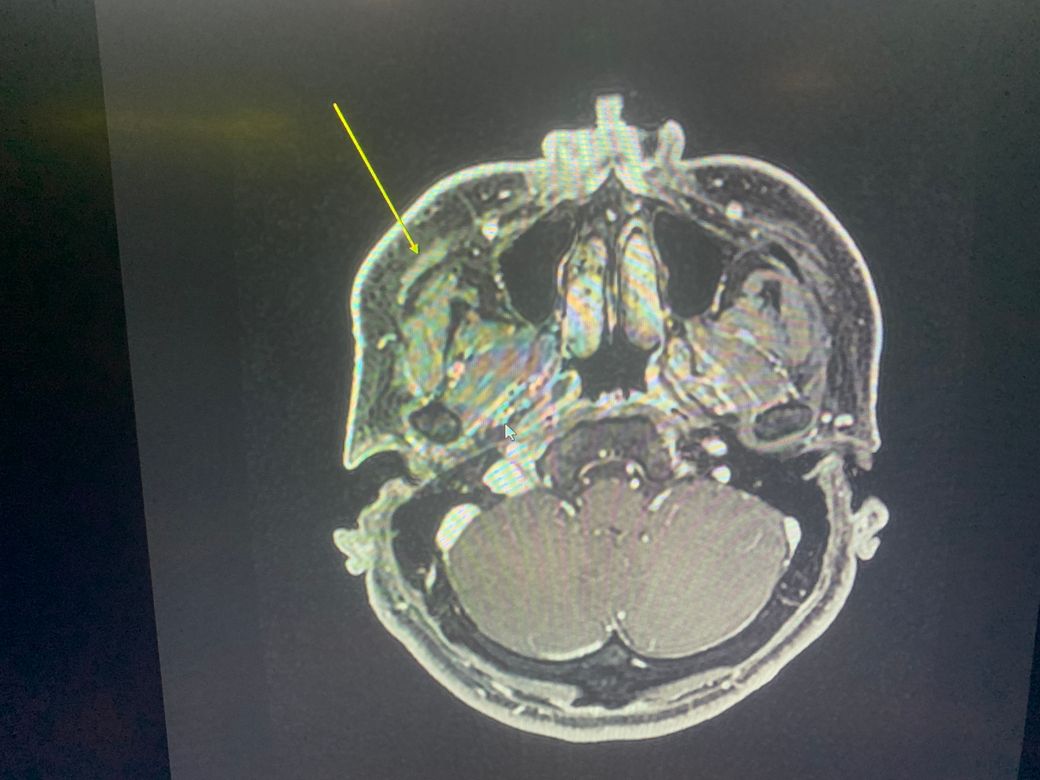

Mri좀 봐주세요 광대뼈아래에 큰소리가 났습니다 소리난 후로 앞광대주변으로 통증이 있어서 mri를 찍었는데 저렇게 하얗게 나왔는데요. 수술로 치료가 가능할까요.

오육년전에 앞광대 바로 아래에서 뭐가 부러지는소리가 나고 지금까지 얼굴에 계속 부종 통증이 있습니다

• 1번 째 사진